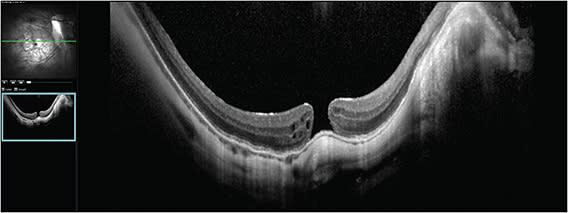

Dr. Vajzovic: This is a case of recurrent myopic macular hole in a 48-year-old male patient who had a long-standing history of degenerative myopia. His axial length is 34 mm. Interestingly, he had prophylactic macular buckle surgery performed in both eyes in 2012. Before seeing this patient, I didn’t know macular buckles were performed prophylactically in the United States. He had cataract extraction done, and unfortunately he developed myopic macular hole in the right eye. He underwent primary vitrectomy and membrane peeling with shorter-acting gas in 2016. At that time, the hole closed and his vision was back to 20/20. Then the hole reopened a few months later and he underwent secondary vitrectomy and membrane peel. The hole closed again, then 3 years later it reopened and he underwent surgery again with longer-acting gas. Each time a membrane peeling was performed. This time, the hole did not close. On the optical coherence tomography (OCT) taken at presentation, the macular hole size was 200 µm, which is not huge, and edges were everted with cystic changes, which is a good prognostic sign (Figure 1). At this point, he was already on drops and he was tried on topical therapy after the last procedure. However, looking at this, topical therapy alone likely will not be the fix. His visual acuity is 20/64, which is remarkably good after all the prior macular hole surgeries. I was really intrigued by that. I questioned whether that macular buckle was actually well positioned and doing him any good or if it had something to do with the hole reopening. The OCT did not show thick epiretinal membranes or anything more concerning than that. There is quite a myopic fundus with peripapillary atrophy and staphyloma as well.